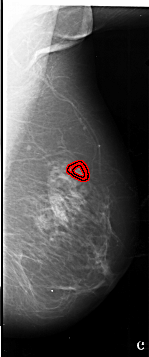

A_1012_1.RIGHT_CC

RIGHT_CC LINES 6541 PIXELS_PER_LINE 2941 BITS_PER_PIXEL 16 RESOLUTION 42 OVERLAY

FILE: A_1012_1.RIGHT_CC.OVERLAY

TOTAL_ABNORMALITIES 1

ABNORMALITY 1

LESION_TYPE MASS SHAPE IRREGULAR MARGINS SPICULATED

ASSESSMENT 4

SUBTLETY 2

PATHOLOGY MALIGNANT

TOTAL_OUTLINES 2

BOUNDARY

CORE